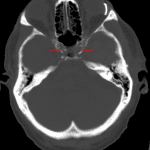

- Associated mass effect with left hemispheric sulcal effacement, left to right midline shift measuring 13 mm at the Foramen of Monro with left subfalcine herniation, near complete effacement of the left lateral ventricle, and left uncal herniation with partial effacement of the suprasellar cistern and mass effect upon the midbrain

- Bilateral mixed density cerebral convexity extraaxial collections measuring up to 8 mm in thickness on the left

- Right greater than left mastoid effusions

- Glaucoma reservoir along the lateral aspect of the left globe

Large acute parenchymal hematoma centered in the left temporal resection bed measuring 8.5 x 6 x 5.5 cm (volume = 140 mL) with surrounding vasogenic edema. Associated mass effect with left hemispheric sulcal effacement, left to right midline shift measuring 13 mm at the Foramen of Monro with left subfalcine herniation, near complete effacement of the left lateral ventricle, and left uncal herniation with partial effacement of the suprasellar cistern and mass effect upon the midbrain. No cerebellar tonsillar herniation.

Sequela of recent left pterional craniotomy with bilateral mixed density cerebral convexity extraaxial hematomas versus hematohygromas measuring up to 8 mm in thickness on the left.